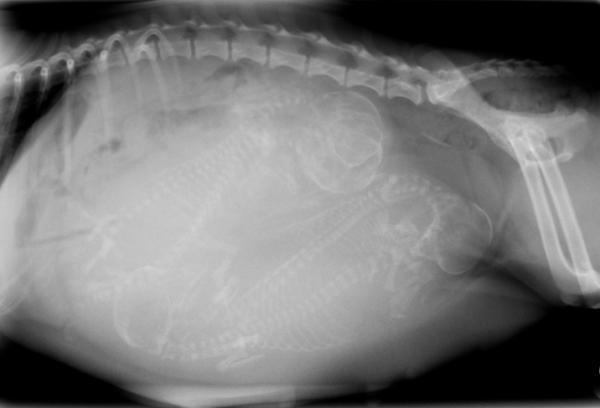

Para saber de cuánto está embarazada una perra es preciso visitar al veterinario para realizar una ecografía y, tras la exploración, establecer una fecha aproximada de gestación. Tal y como hemos visto al repasar los síntomas de una perra embarazada, no todas presentan signos de embarazo al principio, por lo que no siempre es fácil intuir en qué momento del embarazo se encuentra. Otras pruebas que realizará el especialista para determinar la duración del embarazo de la perra en función del momento de la gestación en el que se encuentre es la propia palpación abdominal y una prueba de ultrasonidos o radiografía.

Por otra parte, podemos pedir cita para una ecografía. En ella, antes de la tercera semana, podremos ver a los cachorros. Este dato, que también se obtiene con una radiografía hacia el mes y medio, es importante de cara a saber si el parto ha concluido o no, aunque puede haber algún error. Poco antes de la fecha probable del parto se aconseja otra visita. El veterinario, pero también nosotros, a esas alturas podremos notar el movimiento de los cachorros tan solo apoyando las manos sobre el abdomen. Es buen momento para que nos resuelva dudas sobre el parto y anotemos el número de las urgencias veterinarias, por si acaso.